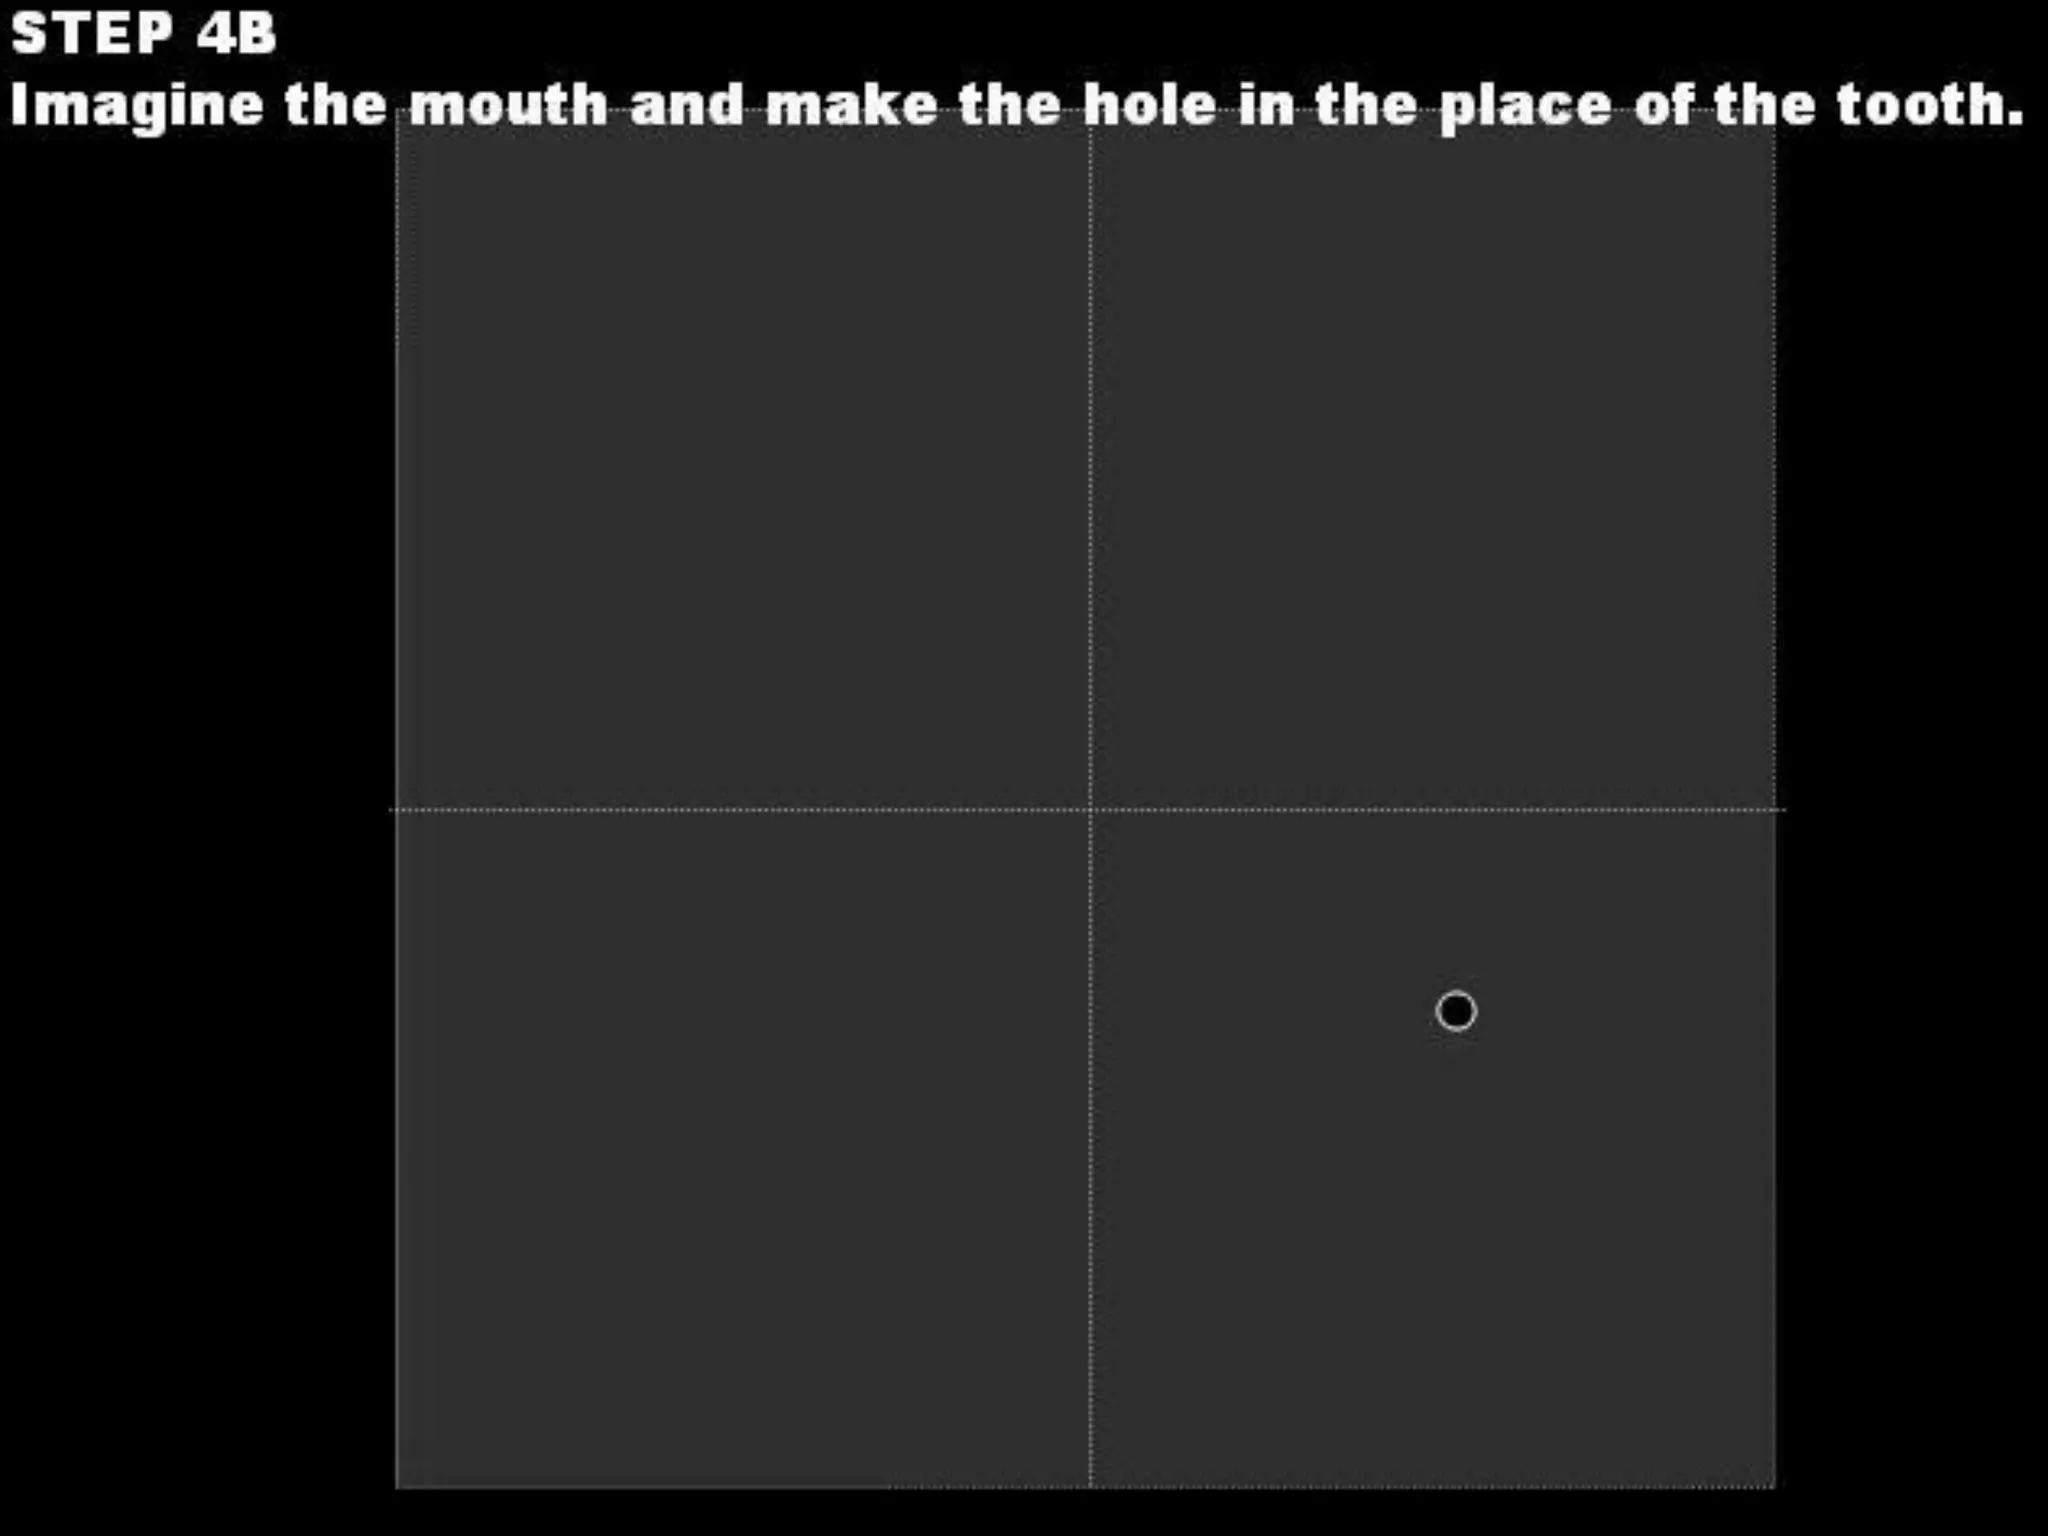

This document discusses the materials and components used for rubber dam isolation in dentistry. It describes the different types of rubber dam materials including color options and napkins to absorb moisture. It also outlines the tools needed such as punches to make holes, templates and stamps to guide hole placement, clamps to secure the dam, and other accessories like wedges and lubricant. Finally, it provides guidance on punching holes for different types of teeth and properly placing clamps in the rubber dam.